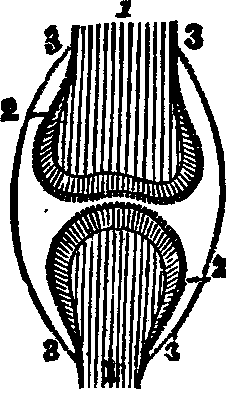

Fig.

17. Anatomy of a joint, 1, 1. Bones of a joint. 2, 2. Cartilage. 3, 3, 3, 3. Synovial

membrane.

Fig. 18. Anatomy of knee joint. 1. Lower

end of thigh-bone. 3. Knee-pan. 2, 4 Ligaments of the

knee-pan. 5. Upper end of the tibia, or shin-bone. 6, 12.

Cartilages.

The formation of the joints requires not only bones, but also [pg

29]cartilages, ligaments, and the synovial membrane, to complete the

articulation. Cartilage is a smooth, elastic substance, softer than

bone, and invested with a thin membrane, called perichondrium. When

cartilage is placed upon convex surfaces, the reverse is true. The

Ligaments are white, inelastic, tendinous substances, softer than

cartilage, but harder than membrane. Their function is to bind together the

bones. The Synovial Membrane covers the cartilages, and is then

reflected upon the ligaments, thus forming a thin, closed sac, called the

synovial capsule.

All the synovial membranes secrete a lubricating fluid, termed

synovia, which enables the surfaces of the bones and ligaments to

move freely upon one another. When this fluid is secreted in excessive

quantities, it produces a disease known as "dropsy of the joints." There

are numerous smaller sacs besides the synovial, called bursæ

mucosæ, which in structure are analogous to them, and secrete a

similar fluid. Some joints permit motion in every direction, as the

shoulders, some in two directions only, as the elbows, while others do not

admit of any movement. The bones, ligaments, cartilages, and synovial

membrane, are supplied with nerves, arteries, and veins.